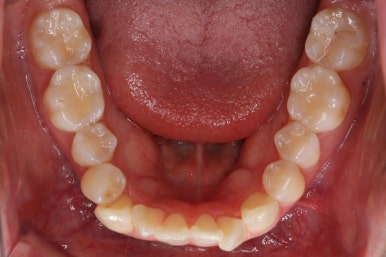

다시 이번 환자분으로 돌아가, 입 안모습을 보시겠습니다.

부산무턱교정 키다리아저씨치과에서 처음 내원하셨을 당시의 입 안의 모습입니다.

아래턱이 작아서 상대적으로 윗니들이 많이 돌출되었고, 뻐드러져 있습니다. 윗니들이 배열되어 있는 형태도 V자에 가깝게 입천장이 좁은 양상입니다.